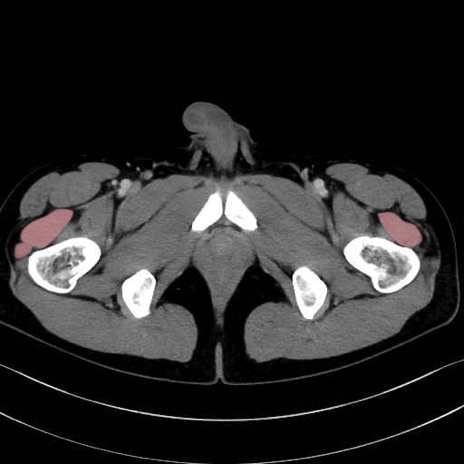

外側広筋 (Vastus lateralis)